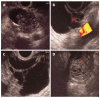

Cystic lesions of the pancreas are being diagnosed with increasing frequency, covering a vast spectrum from benign to malignant and invasive lesions. Numerous investigations can be done to discriminate between benign and non-evolutive lesions from those that require surgery. At the moment, there is no single test that will allow a correct diagnosis in all cases. Endoscopic ultrasound (EUS) morphology, cyst fluid analysis and cytohistology with EUS-guided fine needle aspiration can aid in this difficult diagnosis.